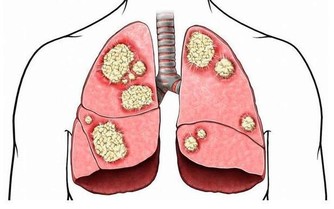

壞膽固醇會在血管形成動脈粥樣硬化斑塊。

斑塊不斷增大,使動脈逐漸狹窄甚至阻塞,就會引起心絞痛、心肌缺血等病。

而當這些斑塊突然破裂脫落,更會迅速堵塞血管,引起急性心肌梗死,

甚至猝死,儼然一枚枚埋在人們體內的「不定時炸彈」。